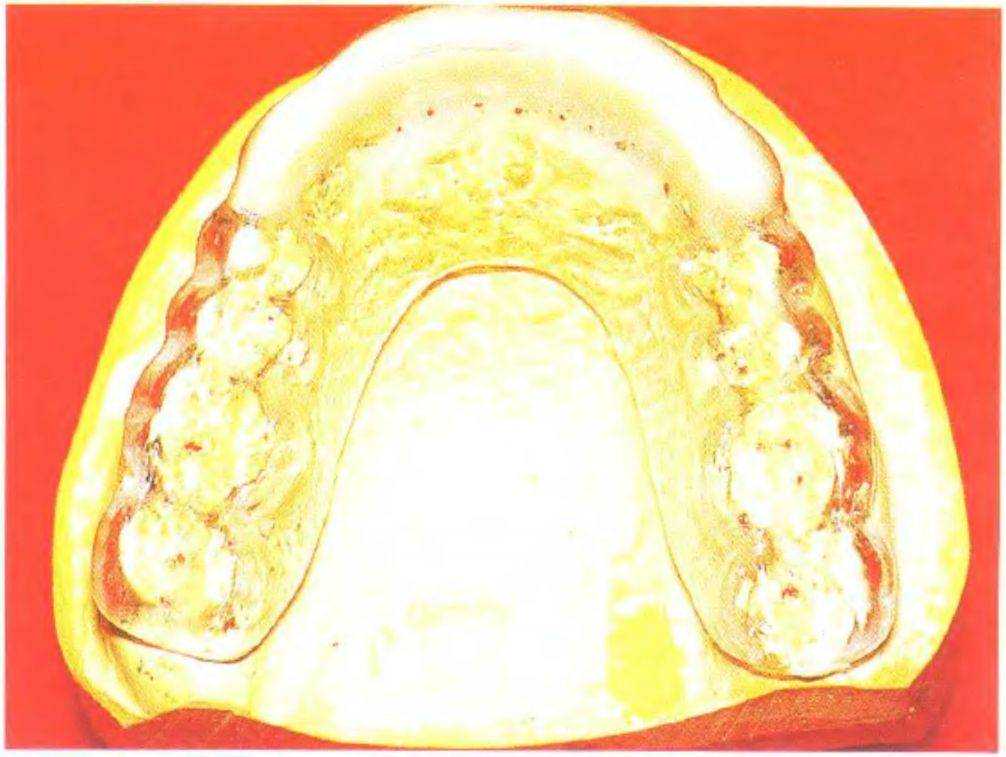

Рис. 3-38а. Каппа, обеспечивающая переднюю направляющую

Рис. 3-38Ь. Каппа в центральном соотношении, обеспечивающая переднюю направляющую

Рис. 3-38д. Каппа в центральном положении плато Шора после селективного сошлифовывания